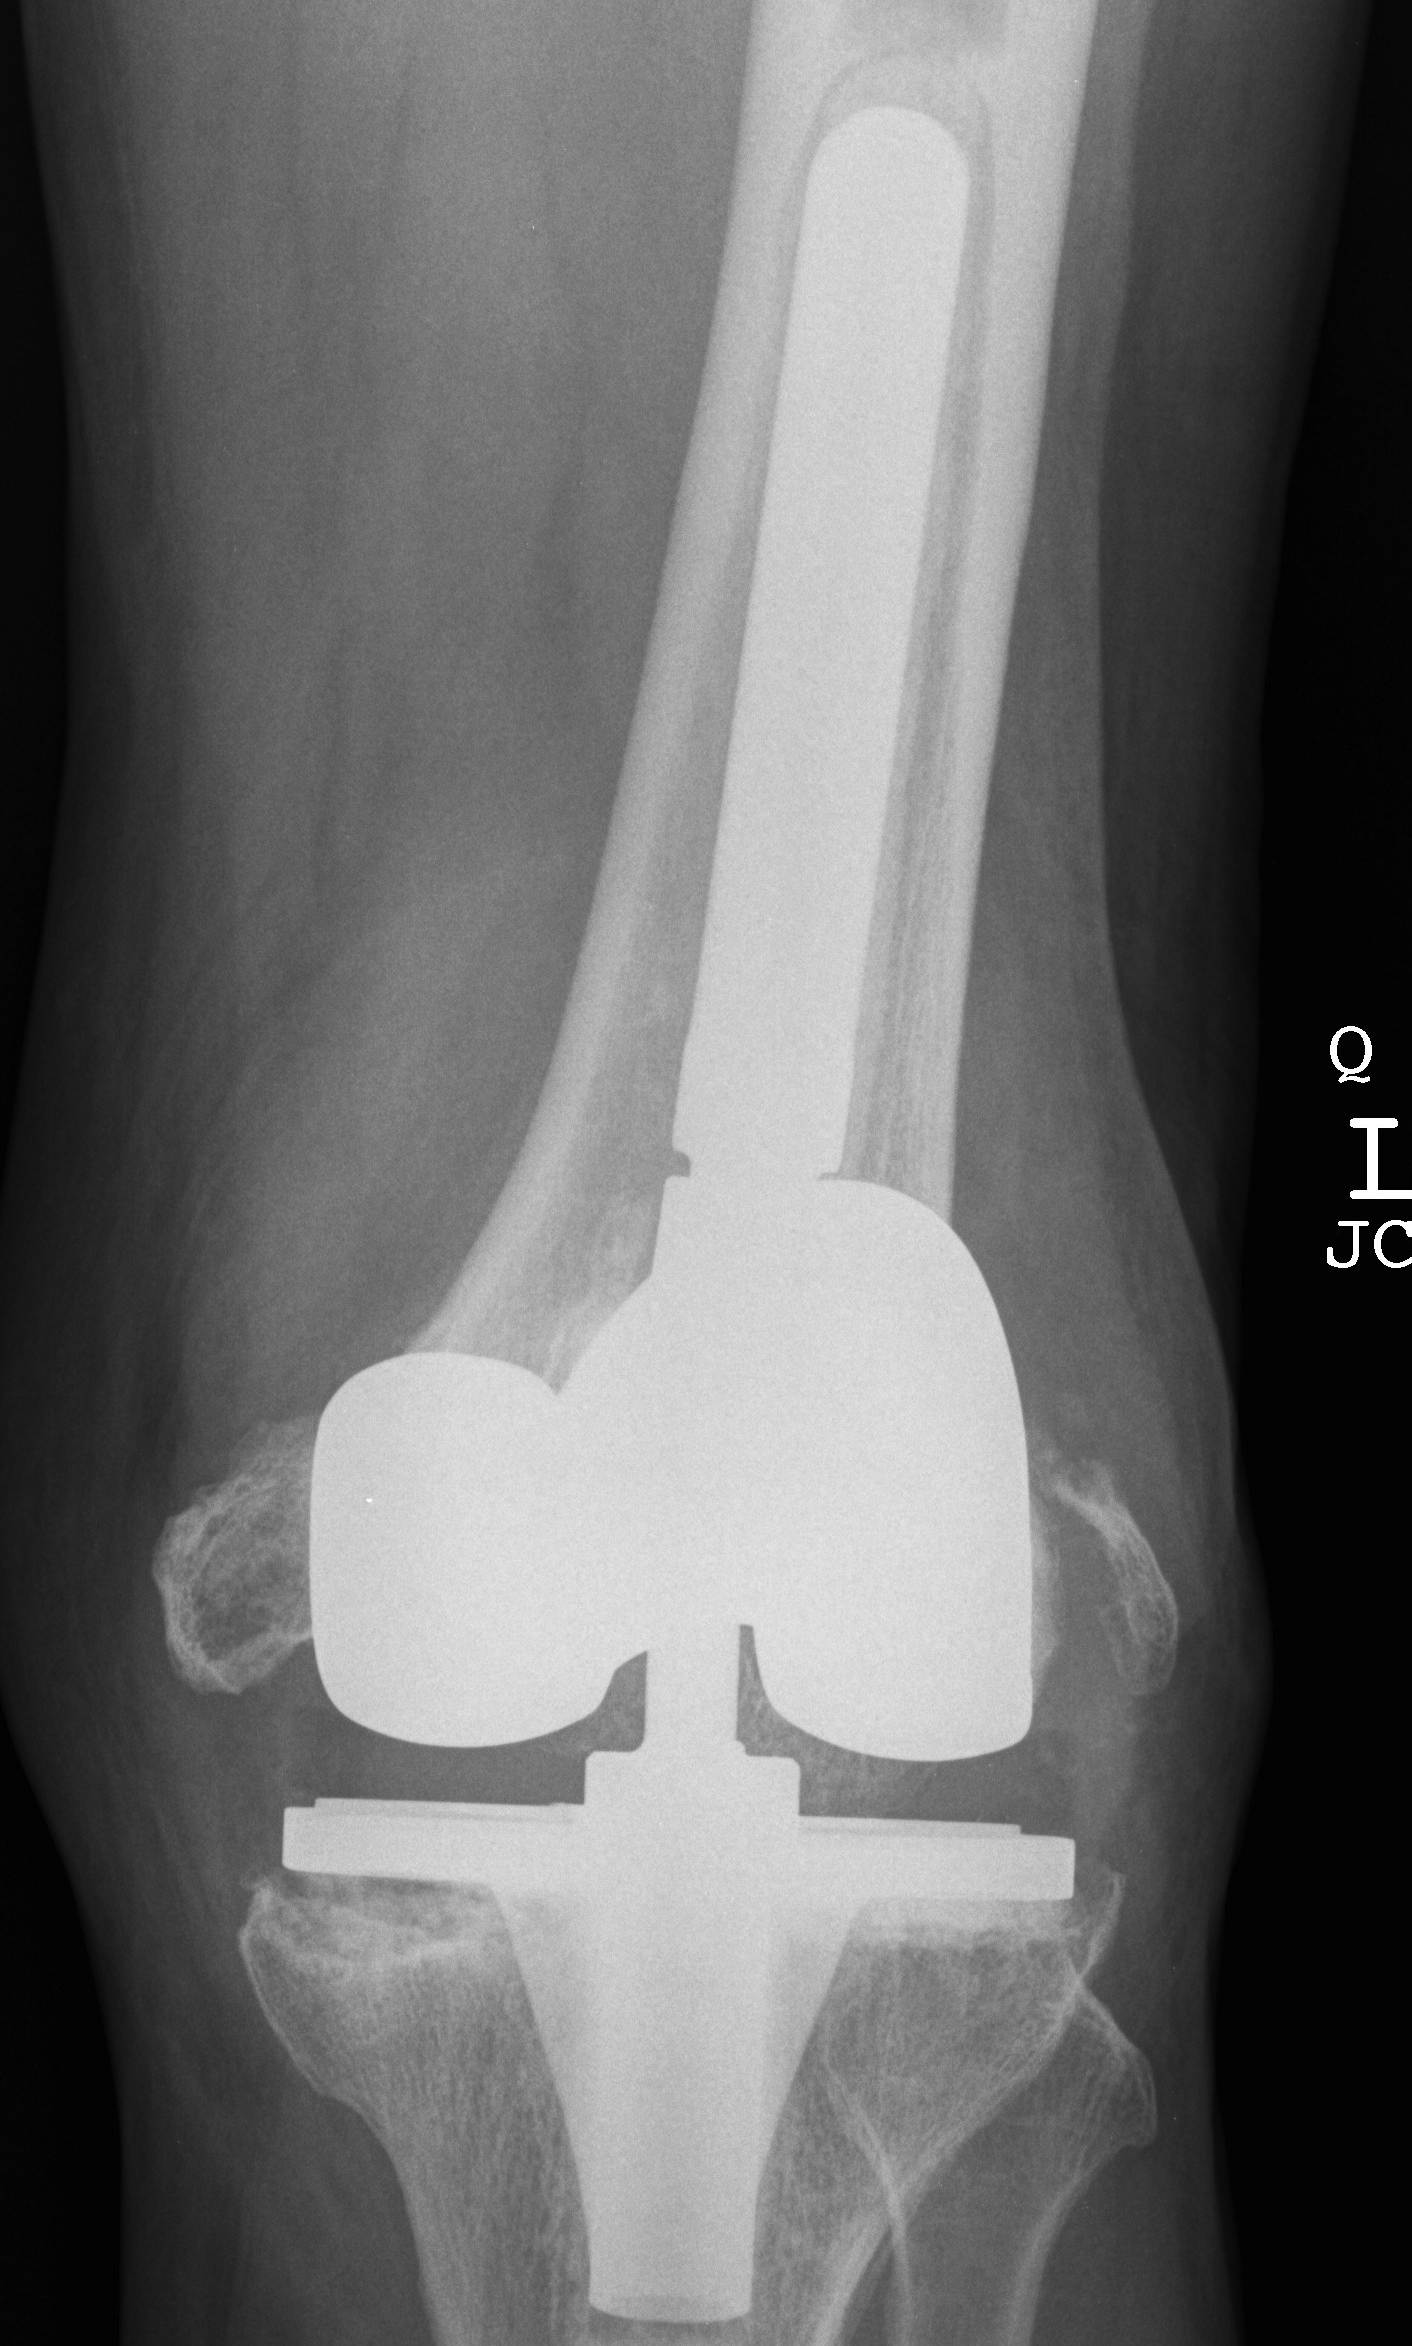

- 184 cemented revision TKR with press fit stems

- significant bone loss

10. Loosening